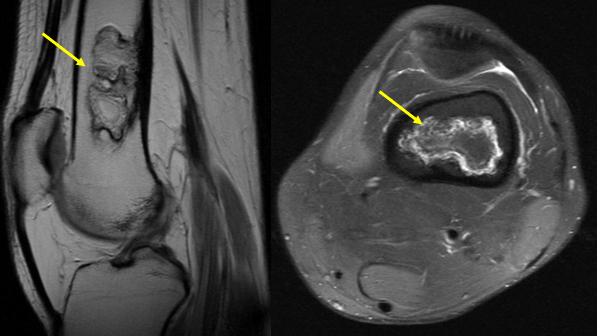

Bệnh nhồi máu xương là một tình trạng nơi xương bị hoại tử do thiếu máu cục bộ, dẫn đến sự phá hủy cấu trúc xương, gây đau đớn, mất chức năng. Đây thường là kết quả của sự suy giảm lưu thông máu tới khu vực xương, dẫn đến sự tổn thương và chết tế bào không thể phục hồi được. Nhồi máu xương có thể được nhận diện thông qua các thay đổi tế bào chất, tế bào nhân, thường được quan sát qua kính hiển vi hoặc hình ảnh học như X quang, CT, MRI.

Đặc điểm hình ảnh của nhồi máu xương thường rõ ràng và có thể nhìn thấy sự suy giảm lưu thông máu, dẫn đến hoại tử xương. Thuật ngữ "nhồi máu tủy" cũng được sử dụng tương đương nhưng ít phổ biến hơn, thường liên quan đến các trường hợp nơi máu không đủ để cung cấp cho tủy xương. Trong một số trường hợp, thuật ngữ này có thể ám chỉ đến sự hoại tử xương tại đầu xương, nhưng không dùng để mô tả hoại tử xương dưới sụn.

Biến chứng của nhồi máu xương có thể là khối u, bao gồm u mô bào sợi ác tính, sarcom xương, sarcoma xơ xương. Khối u angiosarcoma xương, mặc dù hiếm gặp, thường xuất hiện quanh đầu gối, nhưng lại có thể gây viêm nhiễm mô mềm, viêm tủy xương. Ngoài ra, để chẩn đoán và phân biệt nhồi máu xương với các bệnh lý khác, cần phải thực hiện các xét nghiệm hình ảnh, đối chiếu với các đặc điểm đặc trưng của bệnh.